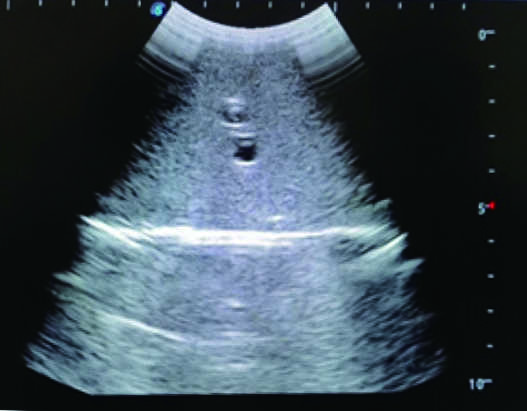

2)  Real clinical ultrasound images with clear anatomical structures like intestines, part of the liver, arteries and veins, etc.